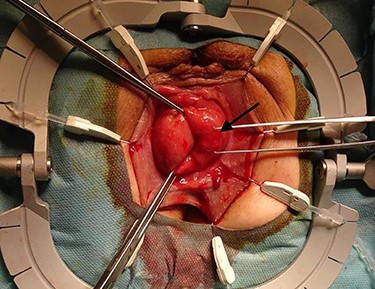

The surgical site was adjusted using a Lonestar retractor and the prolapse was exposed further using Allis clamps (Fig. 2). A monopolar current incision was made slightly above the dentate line, followed by circular dissection of the rectum starting from the ventral aspect (Fig. 3). The entire tumor area between three and six in lithotomy position (3 cm in diameter) was completely reduced (Fig. 4). No penetration was visible on the serosa side. The prolapse was then shortened and a tension-free coloanal anastomosis was created using several Monocryl 4.0 sutures.

Incised rectal prolapse before circular dissection from the rectum. (a) Front view. (b) Rear view.